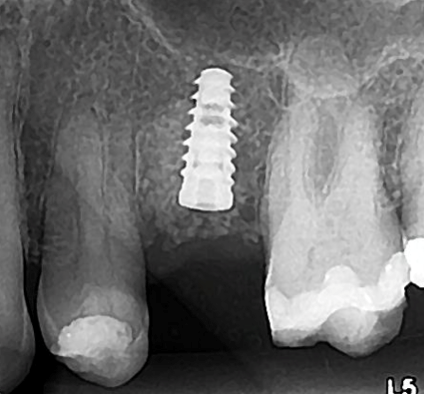

Paciente L.M., 53 anos, apresentava sensibilidade durante a mastigação e relatava mau hálito na região do dente 25. Durante análise clínica, a paciente apresentava sorriso alto (Figura 1). Após análise tomográfica, foi constatada uma perfuração radicular no dente em questão e que a raiz estava em contato com a tábua vestibular, sendo que esta possuía ≥1mm de espessura em seu terço cervical (Figura 2). Após a paciente concordar com o plano de tratamento, foi realizado a instalação imediata de um implante Cone Morse de corpo cônico (Due Cone 3.5×11, Implacil De Bortoli, São Paulo, Brasil), regeneração óssea guiada com osso bovino inorgânico e colocação de uma barreira regenerativa de politetrafluoretileno denso.

O implante Cone Morse de macro-geometria cônica foi instalado 2mm infra-ósseo. Este tipo de plataforma (platform switching) possui vantagens mecânicas e biológicas quando comparado com os implantes HE e HI. Mecanicamente, quando o pilar protético é submetido à forças que simulam a mastigação, existe pouca ou nenhuma micro-movimentação do pilar. Esta característica é fundamental para a não formação de um micro-espaço entre o pilar e a plataforma do implante, protegendo assim o sistema contra a micro-infiltração bacteriana. Com relação à vantagem biológica, pode-se citar o menor diâmetro do componente protético em relação à plataforma do implante. Assim sendo, a crítica zona de contaminação localizada entre o implante e o pilar fica localizada distante do tecido ósseo, gerando assim um vedamento biológico e consequente manutenção do tecido ósseo peri-implantar em longo prazo.

Implantes de macro-geometria cônica são altamente indicados em casos de implante imediato pois a conicidade do implante facilita a obtenção da estabilidade primária, crucial para o sucesso da osseointegração. Neste caso, a obtenção de uma boa estabilidade inicial também foi facilitada pelo posicionamento da raiz no alvéolo (Classe I) (Kan et. al 2011). Com a raiz voltada para a tábua vestibular, após a remoção do dente o osso palatal remanescente propiciou condições para o travamento por causa de sua anatomia mais corticalizada.